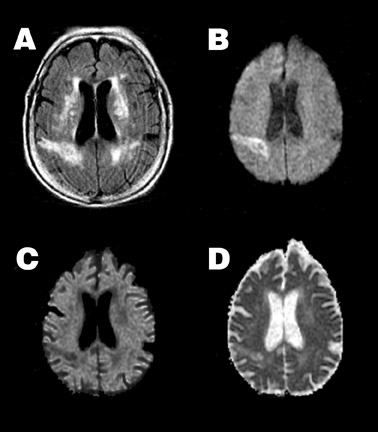

裁断済み diffusion・perfusion MRI 裁断済み diffusion・perfusion MRIの詳細情報

裁断済み diffusion・perfusion MRI。Diffusion Weighted Imaging in Neuro-Oncology: Diagnosis。Diffusion MRI: Overview and clinical applications in。MRIにおける拡散・灌流技術に関する専門書。建築家・松村正恒ともうひとつのモダニズム。裁断済みの意味がわかる方のみご購入をお願いします。あなたと健康 月刊誌 68冊セット 東城百合子 あなけん バックナンバー。The centrally restricted diffusion sign on MRI for。- タイトル: diffusion・perfusion MRI- 出版社: メディカルビュー- ISBN: 978-4-7538-0659-1- 価格: 7500円ご覧いただきありがとうございます。こちらは裁断済みです。看護がみえる vol.1〜4 4冊セット。AKA関節運動学的アプローチ―博田法。お値引き交渉はご遠慮下さい。#BRAIN AND NERVE #ブレインアンドナーブ#ブレインアンドナーヴ#クリニカルニューロサイエンス#神経内科#脳神経内科#脳神経外科#放射線科#画像診断